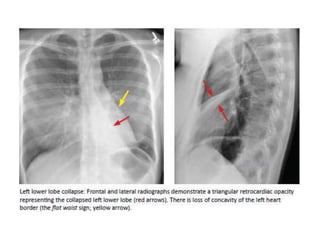

COLLAPSE

• Direct signs of atelectasis are from lobar volume loss

and include:

-Displacement of the fissures

-Vascular crowding.

• Indirect signs of atelectasis are due to the effect of

volume loss on adjacent structures

-Elevation of the diaphragm.

-Rib crowding on the side with volume loss.

-Mediastinal shift to the side with volume loss.

-Overinflation of adjacent or c/l lobes

-hilar displacement

COLLAPSE • Direct signsof atelectasis are from lobar volume loss and include: -Displacement of the fissures -Vascular crowding. • Indirect signs of atelectasis are due to the effect of volume loss on adjacent structures -Elevation of the diaphragm. -Rib crowding on the side with volume loss. -Mediastinal shift to the side with volume loss. -Overinflation of adjacent or c/l lobes -hilar displacement